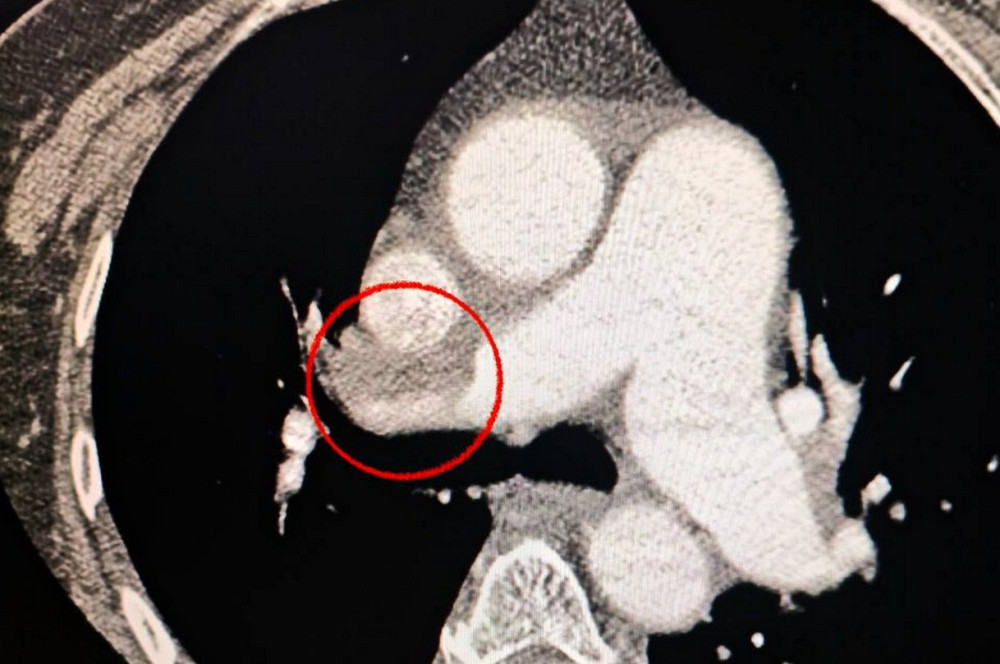

Читати даліУнікальна операція в Одесі, що поєднала лікування інсульту та тромбоемболії легеневої артерії, завершилася успіхом.